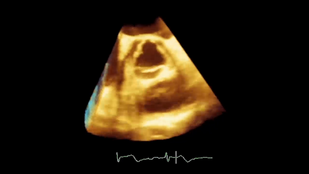

• Обложка: Рис. 2.14 Усиление Видео А Аортальный клапан, коэффициент усиления снижен

• Обложка: Рис. 2.14 Усиление. Видео В Коэффициент усиление повышен